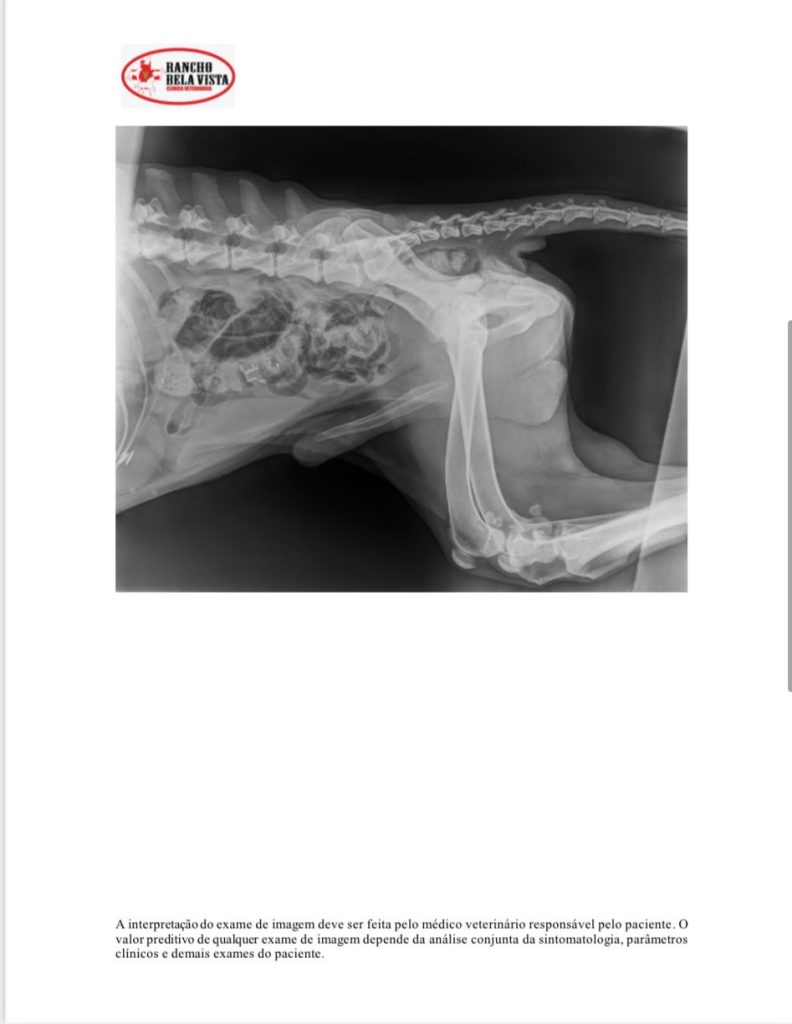

O veterinário Daniel Galante, do Hospital Veterinário, para onde o cão foi levado, disse que as condições eram críticas. Havia pedras e pedaços de ferro no estômago no cachorro.

“Ele estava praticamente em coma, desidratado, passando fome, muito abaixo do peso, com células sanguíneas reduzidas. Não tinha condições de aguentar uma cirurgia. A hipótese é que tenha morrido por causa dessas condições de saúde. Mas pelo que vemos tudo que o cachorro apresentou, era tratável”, explicou o veterinário.

Moradores ficaram com o animal e acionaram a CPI e a prefeitura de Vitória. A equipe de Bem-Estar Animal da prefeitura de Vitória fez o resgate do animal para o hospital veterinário que tem convênio com o município. No local foi constatado que havia pedaços de ferro e pedras no estômago do pit bull. Ele não resistiu aos ferimentos e morreu.